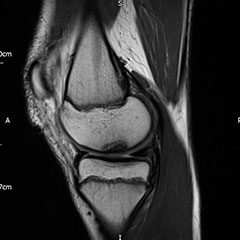

Knee pain

Knee pain is common in physically active adolescents, who can sometimes experience pain in the front and centre of the knee, usually underneath the kneecap (patella). Adolescent anterior knee pain is not usually caused by an abnormality within the knee, but by overuse or a training routine that does not include adequate stretching or strengthening exercises. In most cases, simple measures like rest, over-the-counter medication and strengthening exercises relieve anterior knee pain and allow the young athlete to return to his or her favourite sports.

Sports Injuries

If knee pain is associated with swelling or mechanical symptoms, it may be a sign of other pathology such as OCD (osteochondritis dissecans) or a meniscal injury. OCD occurs when a loose piece of bone and articular cartilage separates from the end of the joint. This piece may stay in place and cause pain or fall into the joint space, causing mechanical symptoms and instability. Children usually between the ages of 10 and 20 experience pain, which is often poorly localised and associated with activity. Swelling may be present, and particularly in a case of an unstable piece, the patient may describe mechanical symptoms such as locking or catching. The outlook is favourable if the skeleton is still growing, but large or unstable lesions may require enforced rest or even surgery. An MRI scan will usually be required to characterise these defects.

Immediate and marked swelling of the knee after injury may indicate a torn cartilage or ligament and should be investigated promptly.

Injuries to the anterior cruciate ligament are also being seen in increasingly younger children, although those under the age of 12 remain more likely to pull out the bone insertion rather than rupturing the ligament itself. Fixation or reconstruction requires careful consideration of the nearby growth plates which contribute the majority of leg growth.